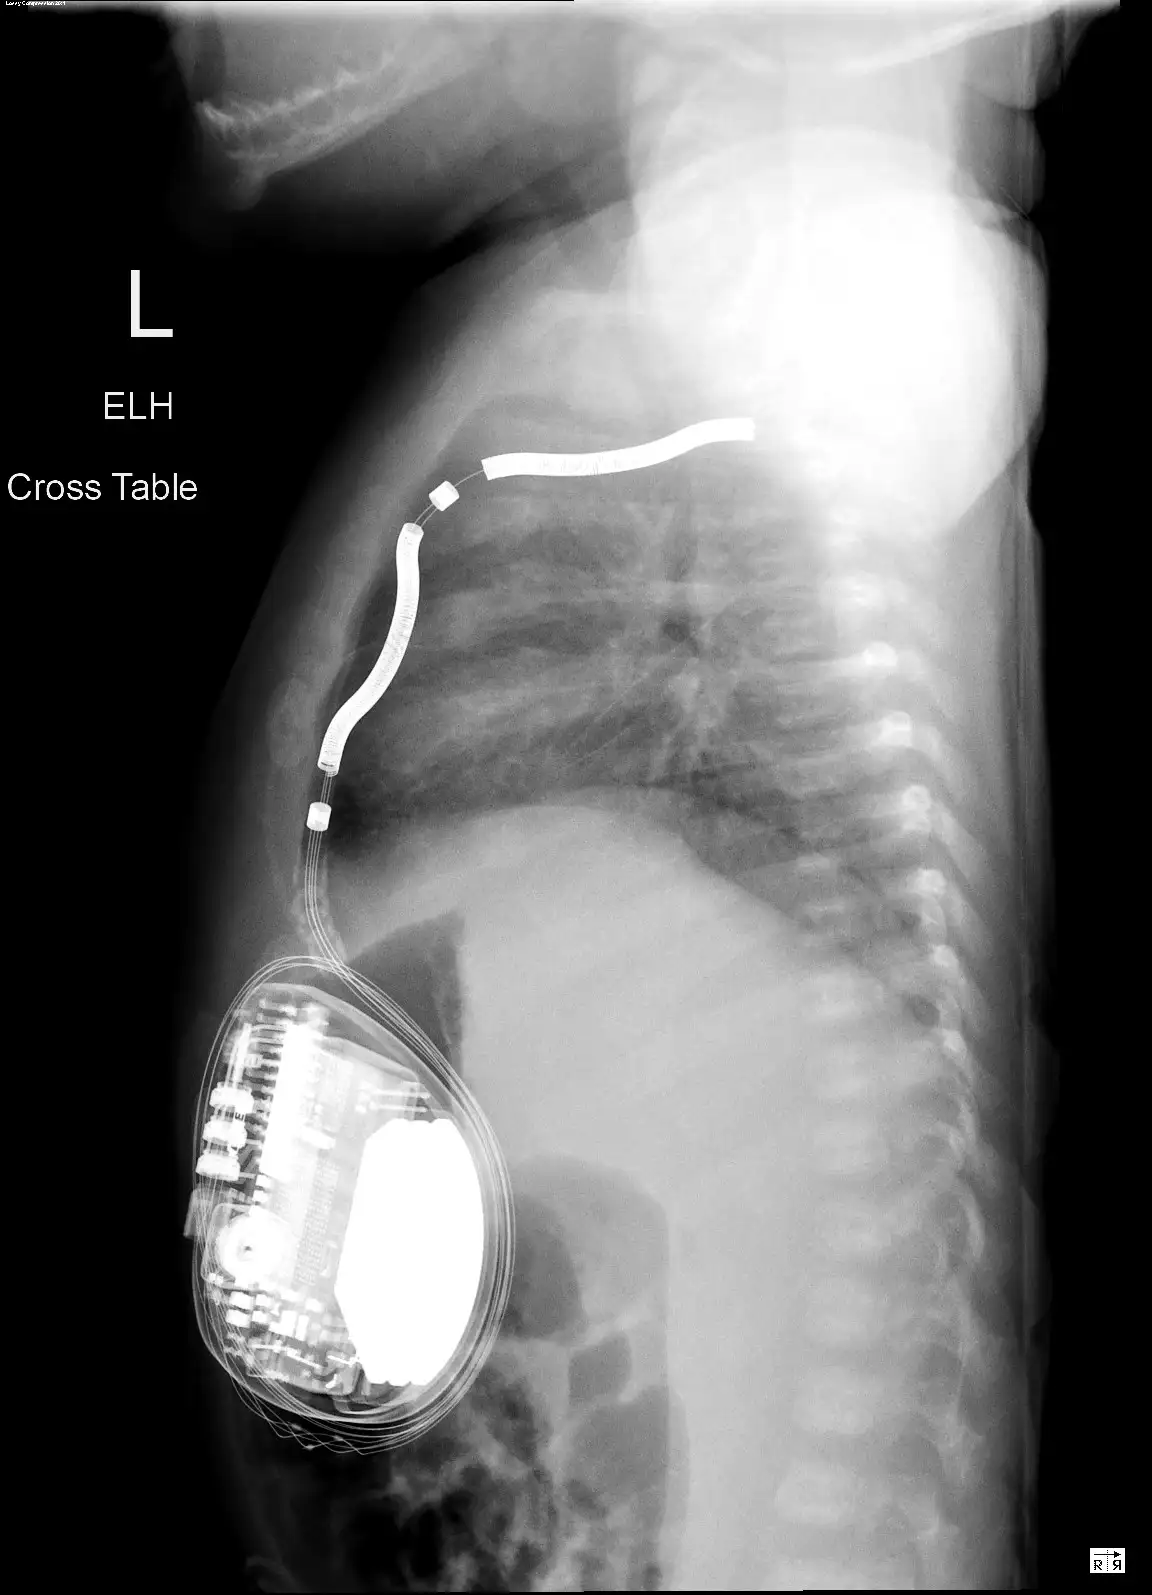

The device and battery were placed in Fletcher’s abdomen below the rib cage, with the single, critical lead wire snaking vertically just below his breastbone to sit just in front of the heart but not directly attached to the heart tissue.

While Fletcher remained under close watch in the hospital’s cardiac ICU, Sassan Hashemi, MD, another member of Division of Pediatric Cardiothoracic Surgery at Cincinnati Children’s, performed a critical task. Using imaging data from Fletcher’s chest CT scan, Hashemi constructed a 3D model of Fletcher’s heart and chest cavity. The process took less than a day.

The 3D results mattered because if the surgical planning had considered only a flat 2D plane, there would not have been enough room to fit a critical 9-cm portion of the device’s lead. But by curving the wire in both vertical and horizontal ways there was just enough room, Connor says.

“This procedure would not have been possible without the 3D model,” Connor says. “It demonstrated that the lead could fit in the desired space and allowed for virtual trialing of multiple positions within the chest.”